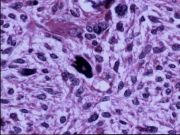

| 2021年12月10日 (五) 13:15 | 14号切片-纤维肉瘤-镜下观3.jpg (文件) |  |

193 KB | Cirno.9 | 基于MsUpload的文件上传 | 1 |